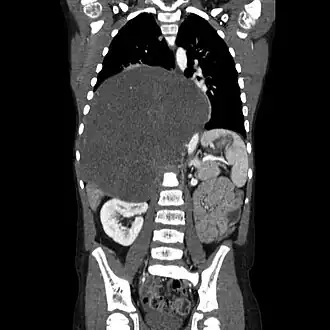

Les ganglioneuromes se situent le plus souvent dans l'abdomen, mais ces tumeurs peuvent se développer partout où l'on retrouve du tissu nerveux sympathique. D'autres localisations courantes incluent la glande surrénale, le rétropéritoine paraspinal, le médiastin postérieur, la tête et le cou[1].

Diagnostic

Les ganglioneuromes peuvent être diagnostiqués par une tomodensitométrie, un IRM ou une échographie de la tête, de l'abdomen ou du bassin. Des analyses de sang et d'urine peuvent être effectuées pour déterminer si la tumeur sécrète des hormones ou d'autres produits chimiques en circulation. Une biopsie de la tumeur peut être nécessaire pour confirmer le diagnostic[3].